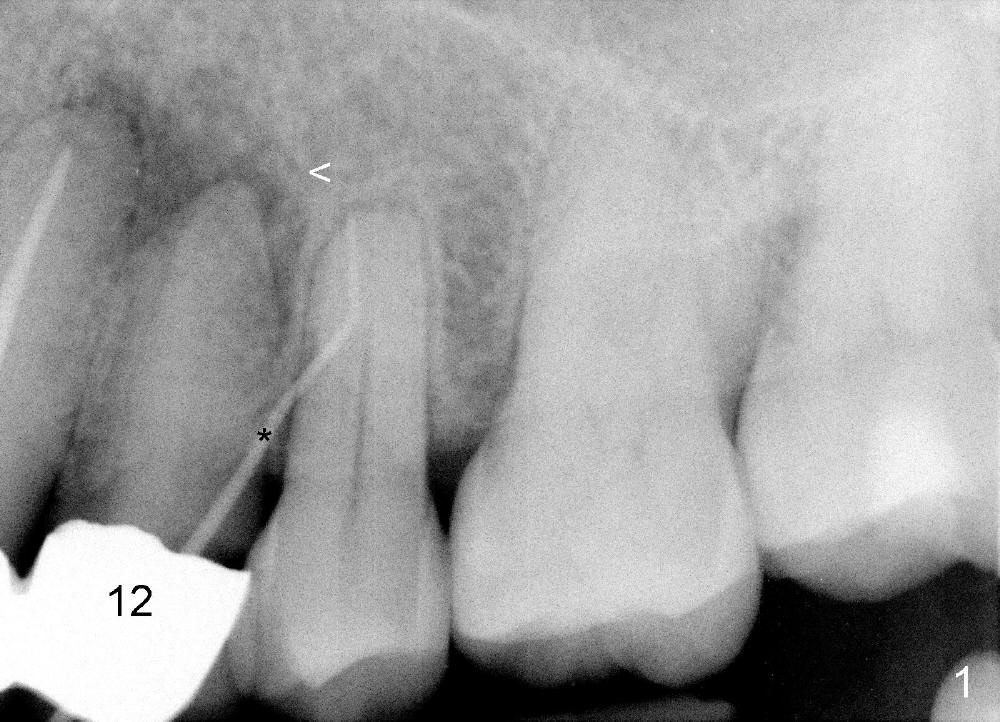

A 74-year-old man has an apical fistula (*: Gutta Percha inserted into the fistula) associated with periapical radiolucency of the tooth #12 (Fig.1 <). The first appointment fails to find the lingual canal, in spite of the fact that there are apparent two canals shown by a preop PA (Fig.2 <). Calcium Hydroxide paste is placed in the debrided buccal canal. Review of previous CT image shows the patent buccal canal (Fig.3 white <) and the apparently obliterated lingual canal (black >).